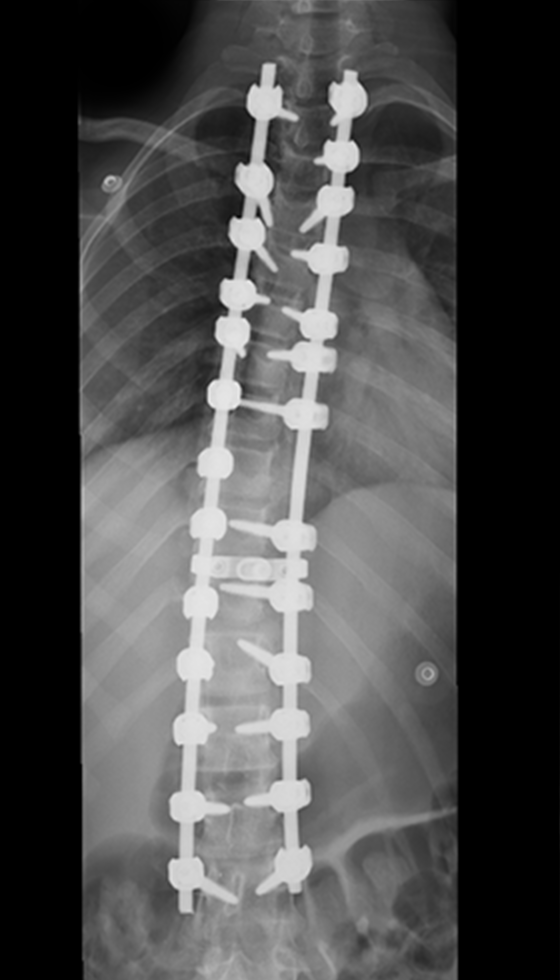

The procedure involves repositioning the spine and securing it with Screws and Rods. Bone graft is then placed so the treated vertebrae gradually heal together into one solid segment. This creates long-term stability, preventing further curve progression and improving overall alignment.

Gallery : Before - After

After

Before